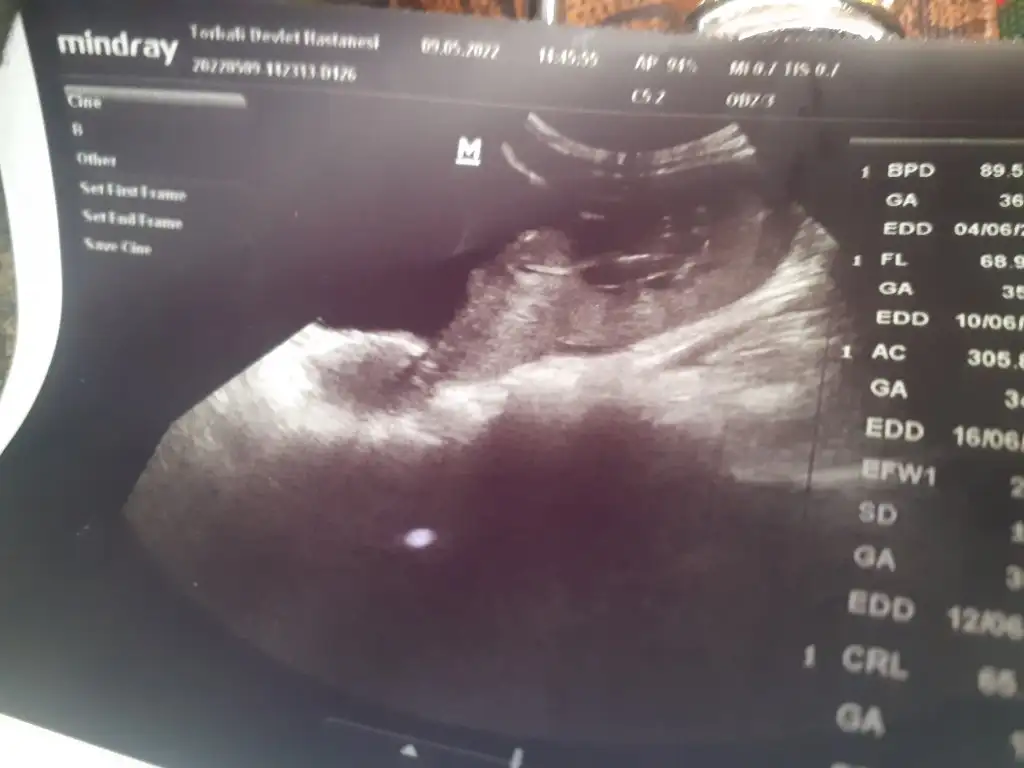

Bakarmisin

• 20220509_153718.webp

20220509_153718.webp

21,1 KB · Görüntüleme: 44

• 20220509_153714.webp

20220509_153714.webp

21,5 KB · Görüntüleme: 39

• 20220509_153706.webp

20220509_153706.webp

23,3 KB · Görüntüleme: 38

• 20220509_153651.webp

20220509_153651.webp

22,5 KB · Görüntüleme: 43